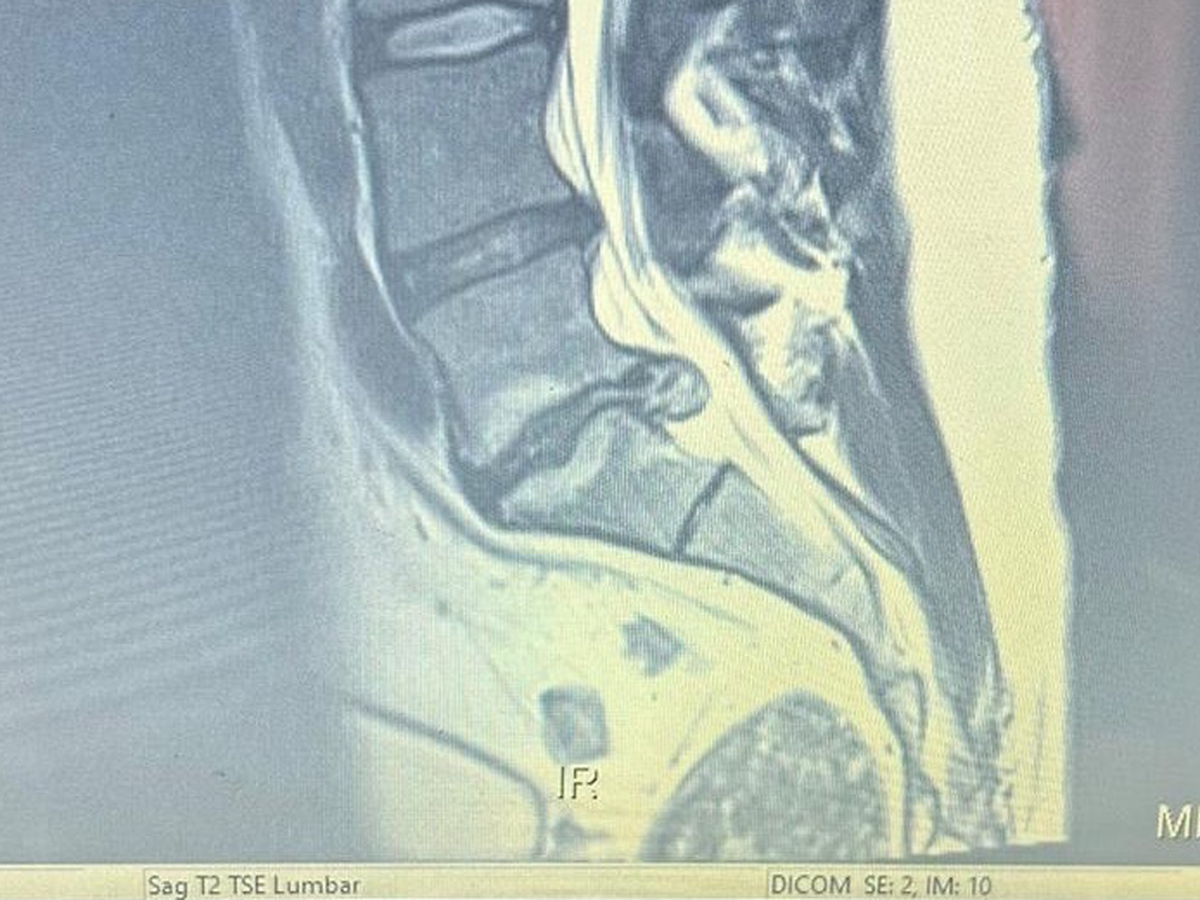

Hey. JoVan is going to Mexico for back surgery. For his back. His sore back. LC1 or 5 or 3 is in bad shape and cartilage or cartage or coralage is shot. Pinched nerve maybe? Hence he has a back that hurts. The doctor in Mexico is confident they can fix him up. For a price of course. Greedy buggers. Joe kind of needs his back to farm and spray and sleep comfortably. And cleaning up after his brother. Surgery is Jan 14. Can you help?